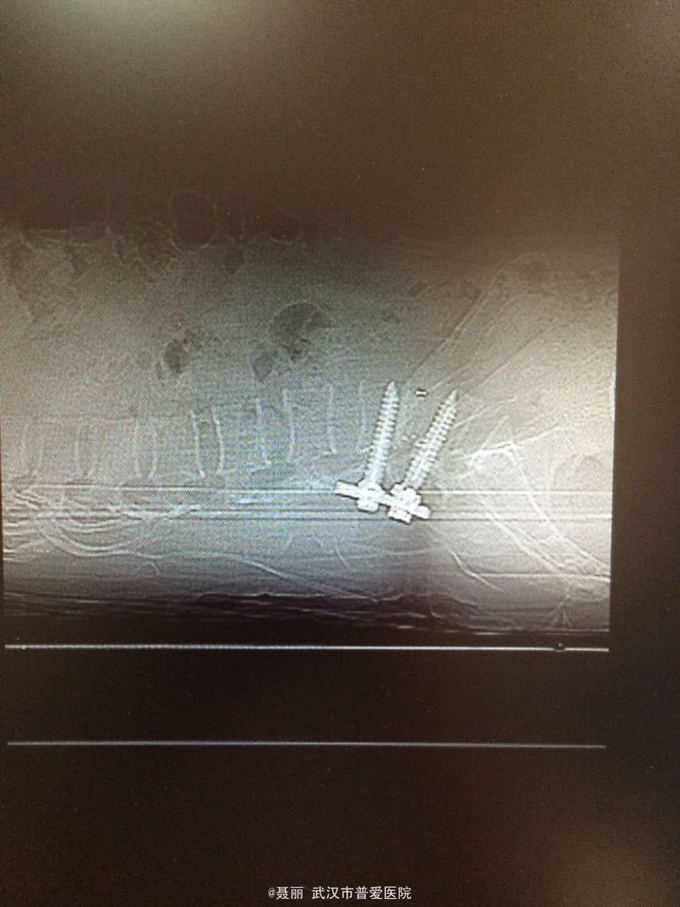

初步诊断:腰椎滑脱症 治疗计划:1、完善相关检查:胸片、心电图,血常规,尿常规,肝肾功能电解质、术前全套 2,活血化瘀扩管治疗。卧床休息。 L4滑脱复位+L4/5椎间盘摘除、椎管减压+椎间cage3植骨融合术

:平卧位休息,加强双下肢主,被动活动,加强直腿抬高锻炼及腰背肌锻炼。2.可佩戴腰部支具逐步下地活动 ,避免弯腰负重,服用营养神经药物治疗,一个月后复查 恢复良好